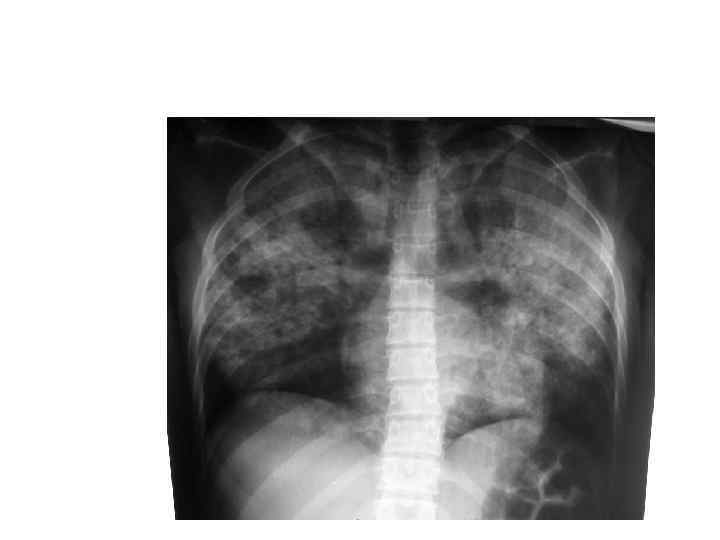

Особенности туберкулеза у ВИЧинфицированных больных • ВИЧ-инфекция повышает в 100 раз риск заболеть туберкулезом. • Активный туберкулез приводит к повышению вирусной нагрузки и прогрессированию ВИЧ. • У больных с низким уровнем СД 4+ симптомы ТБ становятся атипичными (поражаются нижние и средняя доли легких, часто внелегочные формы туберкулеза)

ТБ ТБ/ВИЧ

Особенности клинического течения туберкулеза у ВИЧ-инфицированных: - остропрогрессирующее течение; - диссеминированный или милиарный ТБ с вовлечением лимфатической системы, серозных и мозговых оболочек, ЖКТ; - высокий уд. вес внелегочных форм (в зависимости от выраженности иммунодефицита - от 20 до 70%); - низкая туберкулиновая чувствительность; - высокий уд. вес лекарственно-устойчивых форм туберкулеза (60% и более); - высокая контагиозность больных.